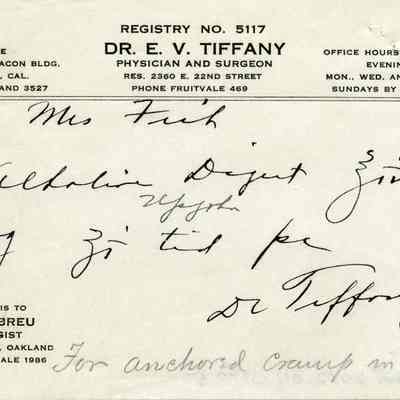

Bill Bill

Bill Bill

Bill Bill

Bill Bill

Bill Bill

Bill Bill

Bill Bill

Bill Bill

Bill Bill

Bill Bill

Bill Bill

Bill Bill

Bill Bill

Bill Bill

Bill Bill

Bill Bill

Bill Bill

Bill Bill

Bill Bill

Bill Bill

Bill Bill

Bill Bill

Bill Bill